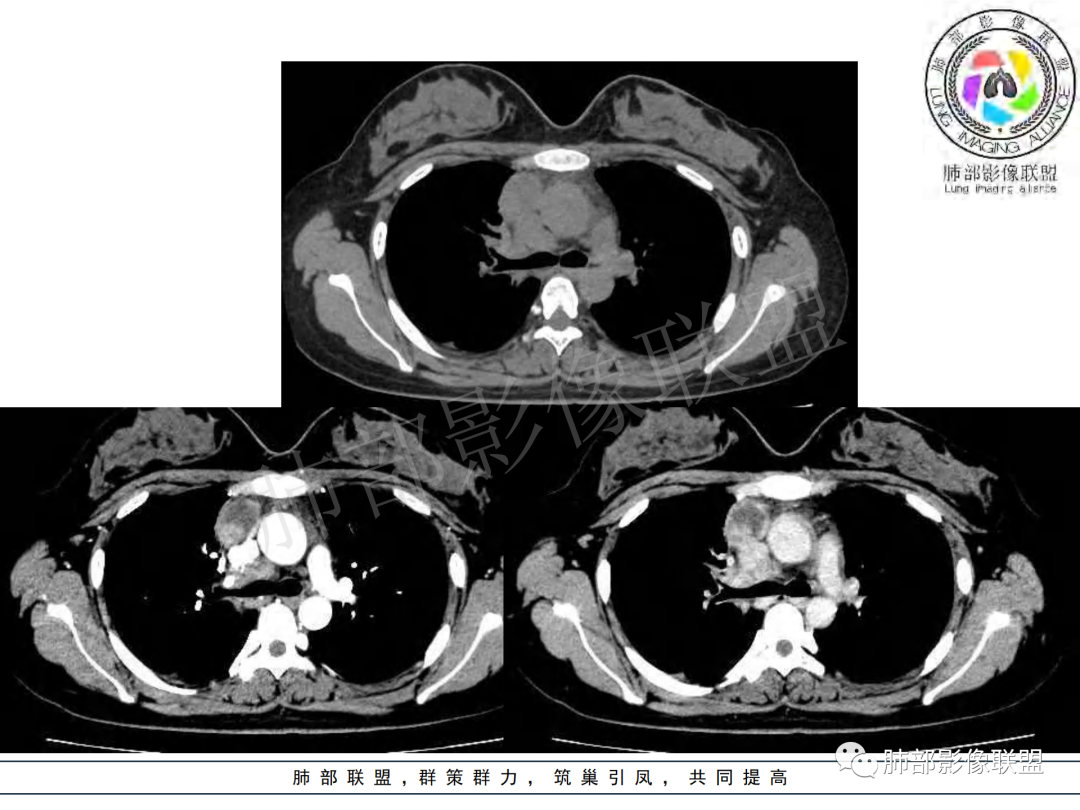

纵隔多组及右侧肺门多发肿大淋巴结,部分融合,不均匀强化,内见斑片状坏死区及环状强化,后者坏死边界尚清晰,肺门区肿大淋巴结与肺组织边界不清,年轻女性,8个月病史,发热首发症状,考虑淋巴结核并向肺内侵及(破溃?),鉴别淋巴瘤

女,20,病程长达8月,发热、胸痛、右侧胸腔积液病史。胸部CT:右肺门旁不规则肿块影,右中间支气管腔内结节,纵隔多发淋巴结肿大;强化不均匀,灶性坏死灶,环形强化;右侧少量胸腔积液并局部肉芽肿样突起。年轻女性,长病程,多部位,考虑慢性炎症,结核?鉴别肿瘤。

年轻女性,慢性病程,发热、胸痛。右肺门旁不规则肿块影,纵隔多发淋巴结肿大;强化不均匀,环形强化;右侧少量胸腔积液;首先考虑结核,鉴别肿瘤,结节病。

右肺门及纵膈多发淋巴结肿大,部分融合,密度不均,部分呈环形强化,年轻女性,病史长,发热,考虑淋巴结结核

慢性病程,前纵隔右肺门旁多发淋巴结肿大;强化不均匀,环形强化;右侧少量胸腔积液;考虑结核,鉴别结节病。

青年女性,发热、胸痛、右侧胸腔积液病史,病程8个月。曾多次抗炎后均有好转。CT:右肺门旁肿块影,双侧胸膜结节,纵隔多发淋巴结肿大,边缘模糊;增强渐进性明显强化,纵膈淋巴结较彻底坏死灶,边缘环形强化。考虑结核,鉴别恶性肿瘤。

女性,20岁。高热、畏寒。右肺上叶近肺门区不规则肿块,周围斑点、片小结节影伴肿大淋巴结,肿块包绕并突入右主支气管腔内,增强后肿块不均匀强化,淋巴结环形强化中心低密度,考虑结核。

无典型结核病中毒症状的成人纵隔淋巴结结核的文献报道不在少数,因此,当临床中遇到症状不典型的患者时,不能轻易排除结核病的诊断,胸部增强CT对本病的诊断与鉴别诊断有一定价值。增强CT扫描时,肿大的淋巴结呈典型的边缘强化或分割样强化,这是纵隔淋巴结结核极具特征性表现,其强化形式与淋巴结内血管及肉芽组织数量及分布有关。淋巴结环形强化或分割样强化的病理基础是淋巴结外周或液化区分隔带有毛细血管丰富的肉芽组织,而无强化的液化区则为无结构的干酪样坏死物质。

本例患者,年轻女性,慢性病程,多次抗感染治疗效果不佳,实验室检查示白细胞及中性粒细胞不高,不支持普通细菌感染,虽然肺泡灌洗液X-Pert检测阴性,结合患者胸部CT结核感染亦不能排除,胸部CT主要表现为右侧肺门及纵隔淋巴结肿大,仔细观察不难发现右中间支气管内新生物凸向管腔内,增强扫描,右肺门(10R)及纵隔淋巴结(2R,4R)明显不均匀强化,内部呈不规则低密度无强化区,被周边高强化区包绕(环形强化)的特点,首先应当想到纵隔淋巴结结核诊断。淋巴结分布亦不符合肺部恶性肿瘤迁徙途径。